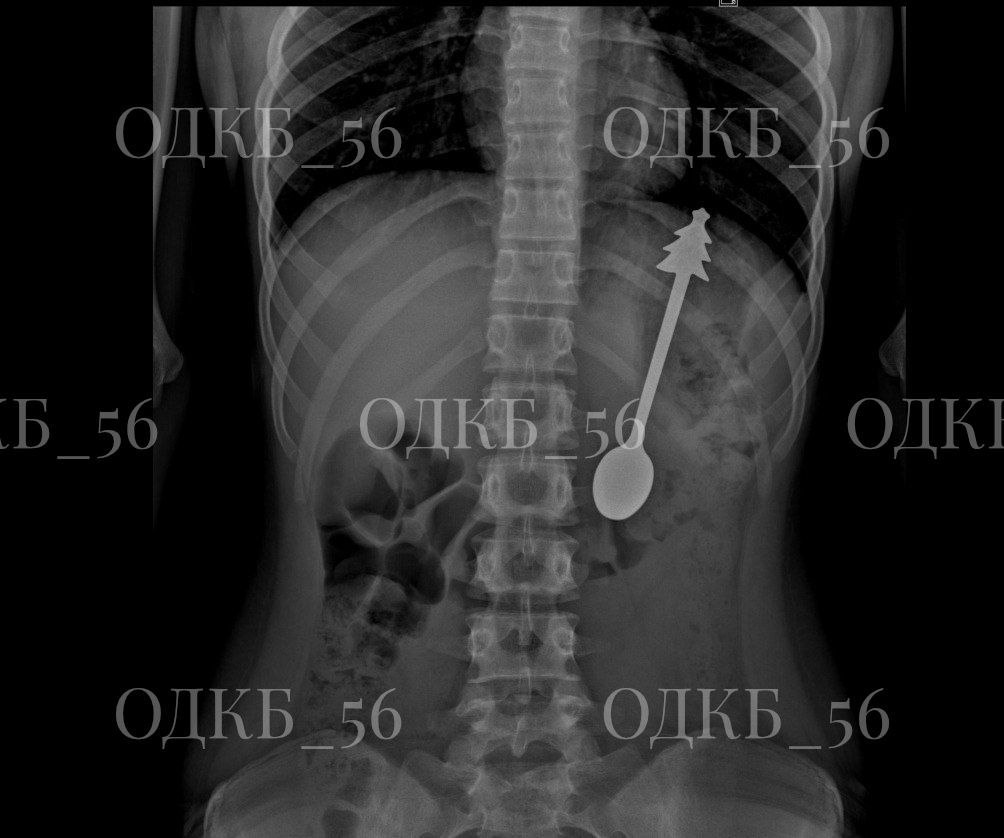

В Оренбурге ребенок проглотил 14-сантиметровую металлическую ложку

Рентген показал, что инородный предмет находится в желудке. Ребенка госпитализировали в детское хирургическое отделение, где было принято решение о проведении эндоскопического вмешательства.